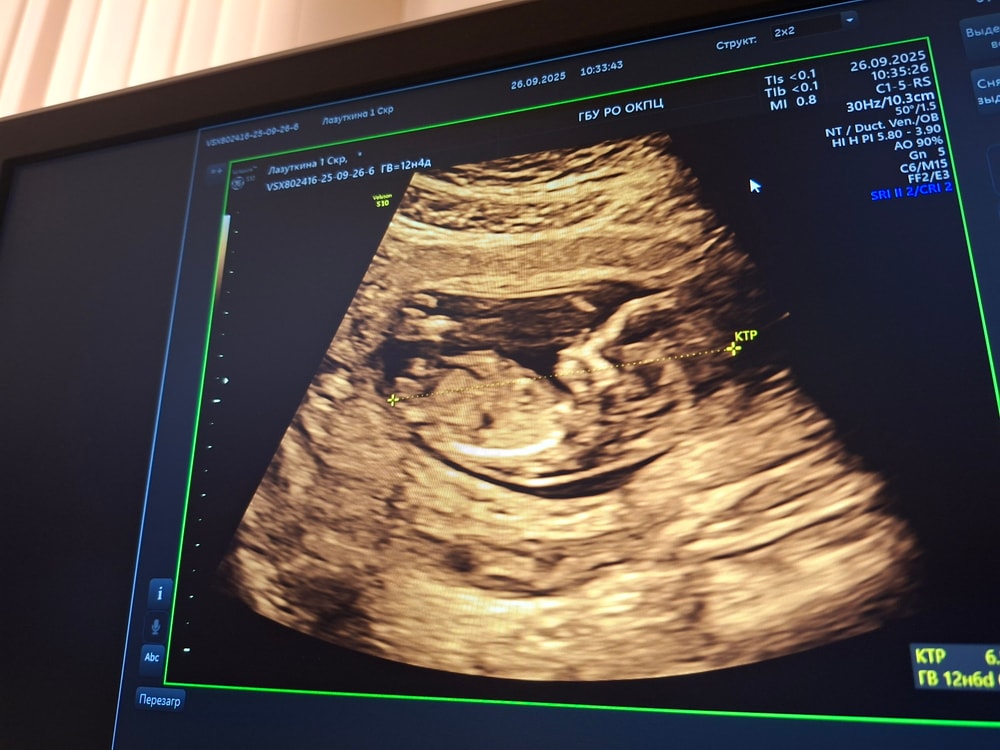

Вот и сходили на 1 скриннинг

Анализы, скринингиБыло очень волнительно, но всё прошло так быстро, что я и не успела заметить. Благо в нашей ЖК добрые врачи и пустили мужа посмотреть на маленькое чудо, и дали сфотографировать с экрана.

Девочки, попробуем погадать, кто же живёт в домике?